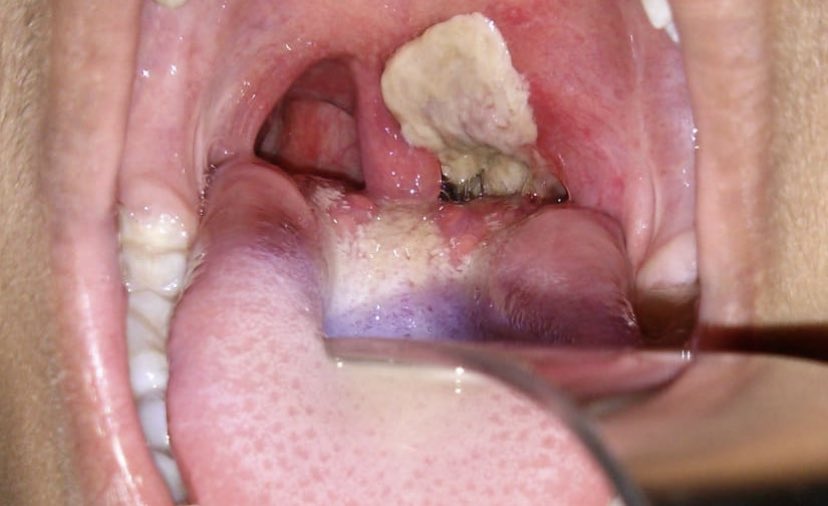

4️⃣ عند توقف صناعة البروتينات، تبدأ الاغشية المخاطية بالاستبدال والتحول الى اغشية مخاطية تحمل داخلها خلايا ميتة وخلايا مناعية وباكتيريا نامية، ليتكون بعدها غشاء جديد يسمى بـpseudomembrane "الغشاء الكاذب"، كما هوا موضح في الصور التالية:

مايميز هذا الغشاء انه ملتصق تماما بالتجويف الداخلي للحلق مما يسبب صعوبة كبيرة جداً في ازالته، كما هوا موضح في الحالة المرفقة: